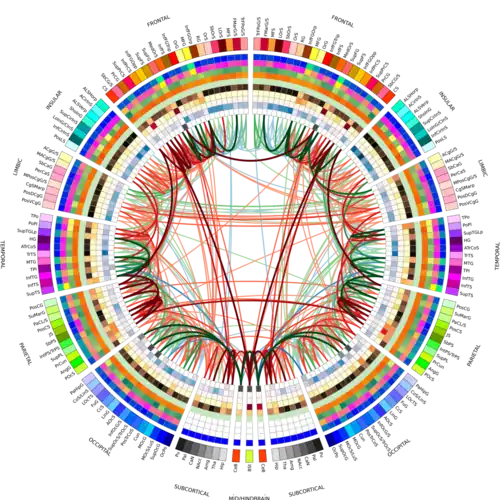

On an individual level, connectograms can be used to inform the treatment of patients with neuroanatomical abnormalities. Connectograms have been used to monitor the progression of neurological recovery of patients who suffered a traumatic brain injury (TBI).[12] They have also been applied to famous patient Phineas Gage, to estimate damage to his neural network (as well as the damage at the cortical level—the primary focus of earlier studies on Gage).[13]

Connectograms can represent the averages of cortical metrics (grey matter volume, surface area, cortical thickness, curvature, and degree of connectivity), as well as tractography data, such as the average densities and fractional anisotropy of the connections, across populations of any size. This allows for visual and statistical comparison between groups such as males and females,[14] differing age cohorts, or healthy controls and patients. Some versions have been used to analyze how partitioned networks are in patient populations[15] or the relative balance between inter- and intra-hemispheric connections.[16]